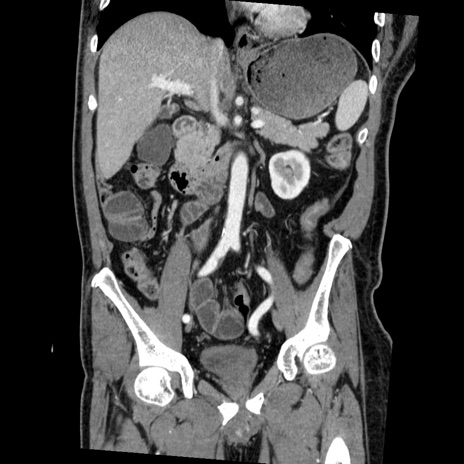

横断像

【症例】50歳代男性

【主訴】腹痛

【現病歴】AVMからの被殻出血のため回復期リハ病棟入院中。 本日午後3時頃急に下腹部痛が出現した。

【既往歴】AVM、被殻出血、虫垂炎、高血圧

【身体所見】意識晴明、左半身不全麻痺、会話の理解は良好、36.5°C、腹部:膨隆、全体に板状硬、下腹部正中に圧痛点あり、反跳痛-、筋性防御不明、右下腹部にope scar

【データ】WBC 9400、CRP 0.06